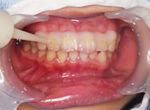

PMTC直後のお口の中の写真です。

染出しして赤くなった部分の汚れを取り除き、舌で歯を触るとツルツルとした感触になります。歯茎の色がきれいなピンク色になって引き締まっています。